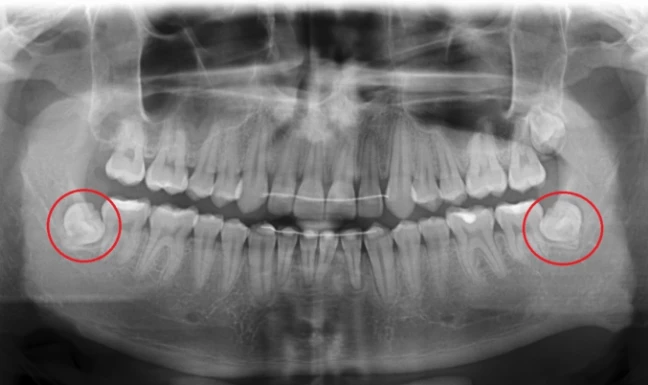

Germektomia jest najczęściej zabiegiem wykonywanym ze wskazań ortodontycznych, polegającym na chirurgicznym usunięciu zawiązka zęba mądrości, czyli "ósemki".

Głównym wskazaniem do germektomii, czyli usunięcia nie w pełni wykształconego zęba, jest zapobieganie stłoczeniom zębów.

Poniżej przedstawiamy germektomię wykonaną u 19-letniego pacjenta przez specjalistę chirurgii stomatologicznej - dr Tomasza Kozioła.